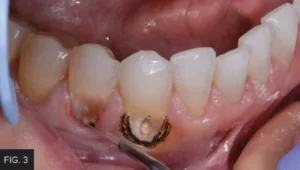

When using a laser, the laser beam is always directed away from the eyes and should always utilize the minimum power setting necessary to accomplish the procedure. If the laser tip drags while the laser is in active mode and is moving across the tissue, the power is too low. Simply increase the power as needed for the smooth removal of the tissue. On the other hand, if there is excess burning or blackening of the tissue, this is an indicator that the power level is too high. In this case, the Bluewave laser was set at a preset power setting of one (1) watt. (FIG. 3)